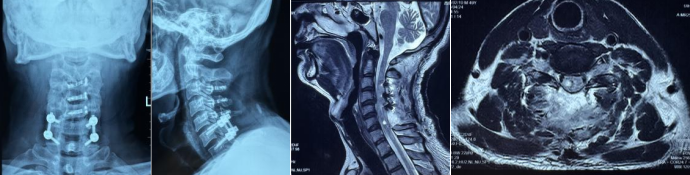

术前

4月20日,49岁的患者王先生,不慎摔伤导致右上肢及右下肢麻木无力,面临严重的致残风险。于是来到了西安市红会医院脊柱病医院老年与创伤脊柱病区就诊。入院完善相关检查后,经诊断,王先生患有颈脊髓损伤、颈髓内出血以及颈椎椎管狭窄。面对这一复杂病情,脊柱病医院创伤与老年脊柱病区主任医师许正伟及其团队,打破传统手术局限,精心设计并实施了一种创新的双重“混合手术”--颈椎后路单开门椎管扩大成形与椎板切除减压植骨融合内固定联合后正中脊髓切开术的手术方案。

该手术方案巧妙结合颈椎开门与椎板切除植骨融合内固定技术,同时联合后正中脊髓切开术,不仅实现了髓内髓外充分减压,还确保了坚强的内固定效果。这种双重“混合”的手术策略,既有效解除了脊髓压迫,保留了患者颈椎的部分活动功能,又实现了可靠的内固定。

术后

手术过程中,许正伟主任团队凭借精湛的技术和丰富的经验,顺利完成了所有手术步骤,术中彻底解除了压迫,术后王先生的神经运动功能得到显著恢复。经过一段时间的康复锻炼,王先生已能在助行器的辅助下下床活动,生活质量得到极大改善。